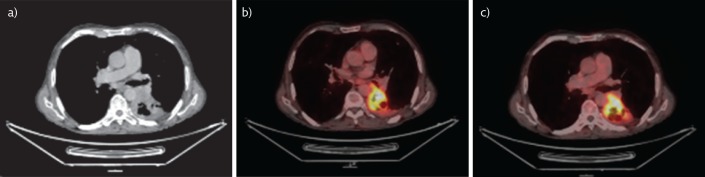

Positron emission tomography/computed tomography scans (figure 1) showed a 2-fluoro-2-deoxy-d-glucose (FDG)-avid (maximum standardised uptake value of 11) heterogeneously enhancing mediastinal pleural based, soft tissue density mass lesion with areas of cavitation noted in the left lower lobe, measuring 6×4.4 cm and encasing the segmental branches of the left lower lobe bronchus. It was closely abutting the pulmonary artery and left inferior pulmonary vein. Faintly FDG-avid and non-avid, subcentimetre-sized pretracheal, precarinal, subcarinal, aortopulmonary window and left tracheobronchial lymph nodes were seen.

Figure 1.

Positron emission tomography/computed tomography scans showed a mass lesion. a) Areas of cavitation were noted in the left lower lobe, encasing the segmental branches of the left lower lobe bronchus. b and c) FDG imaging showed an FDG-avid cavitating mass lesion in the left lower lobe, encasing the segmental branches of the left lower lobe bronchus.